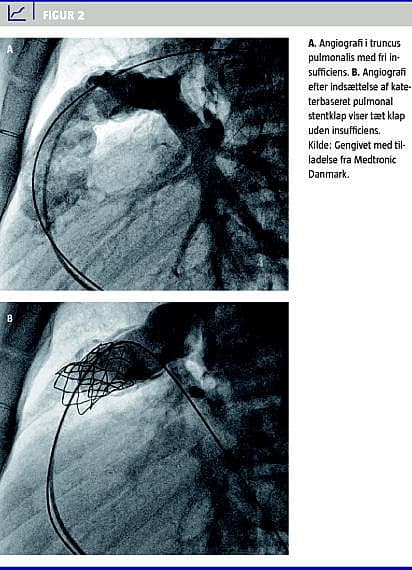

Den pulmonale stentklap er en videreudvikling af den teknik, som Henning Rud Andersen beskrev i 1992 [4]. Et stykke bovint vena jugularis, som indeholder en veneklap, syes ind i en platin-iridium-stent (Melody, Medtronic, Minnesota USA), (Figur 1 A ). Stentklappen krympes manuelt på et indføringskateter (Ensemble, Medtronic, Minnesota USA). Dette -system består af to balloner inden i hinanden. Med adgang via vena femoralis føres indføringssystemet (Figur 1B) med stentklappen til position i den dege-nererede bioprotese under røntgengennemlysning. Herefter inflateres den inderste ballon med 10 ml væske, hvorved stentklappen delvist ekspanderes. Med den inderste ballon inflateret kan stentklappen justeres til den korrekte position, hvorefter den yderste ballon fyldes med 20 ml væske, og stentklappen ekspanderes til fiksation i den eksisterende biologiske klap. Herefter deflateres ballonerne, og indføringssystemet fjernes (Figur 2 A og Figur 2B). Stentklappen findes i en størrelse, som kan ekspanderes til en diameter på 18, 20 eller 22 mm ved hjælp af tre forskellige indføringssystemer.